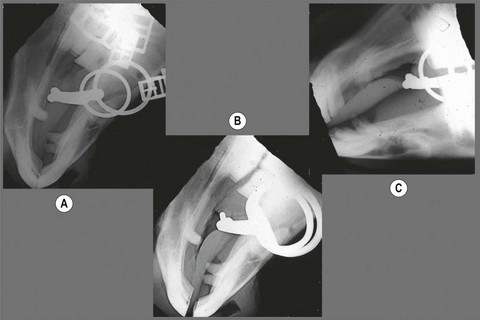

Fig. 3.9 Radiographs of gag bits. (A) Ventrodorsal with no rein pressure. (B) Ventrodorsal under rein pressure. (C) Lateral with no rein pressure. (D) Lateral under rein pressure.

It might be thought that the gag functions to lower the head because tension on the reins places pressure on the poll. But head carriage is more a factor of where the horse finds relief from bit pressure. Since the horse’s mouth is much more sensitive to pressure than his poll, if the gag is used with no auxiliary aids, its net effect is to accentuate the basic head-raising action of a snaffle bit.8 If strong rein pressure is applied to a gag bridle, the bit is pulled relatively far caudally and can severely punish the horse’s tongue, lips and cheeks (Fig. 3.9).